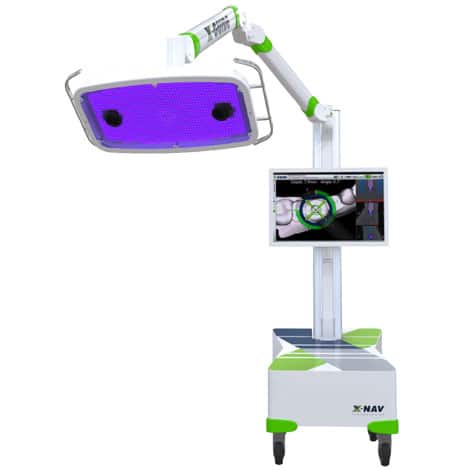

X-Guide®